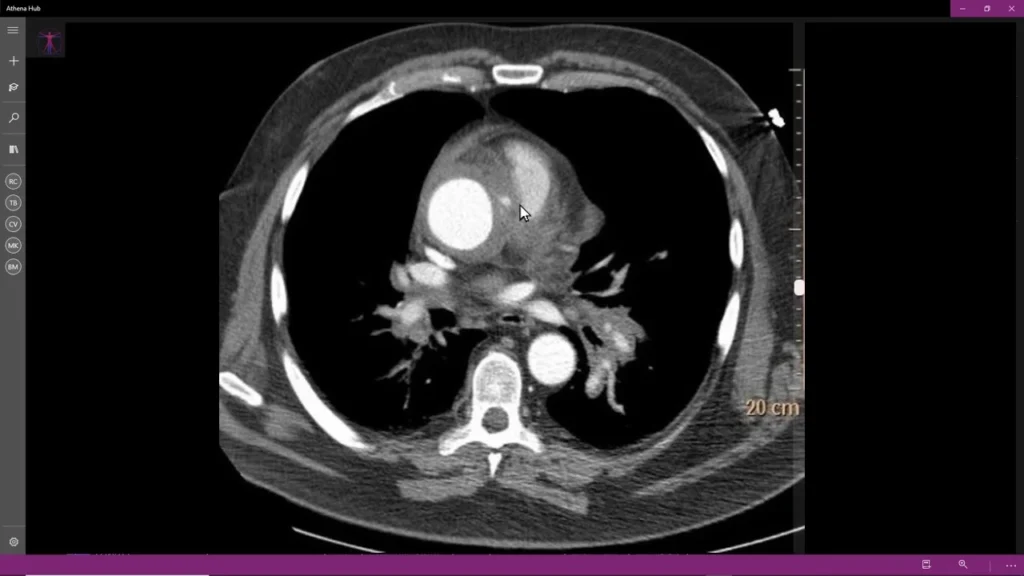

La prevenzione delle sindromi aortiche acute include il controllo dei fattori di rischio come l’ipertensione arteriosa, l’aterosclerosi, il fumo e la storia familiare di malattie cardiovascolari. Se sospetti di avere una sindrome aortica acuta, è fondamentale consultare immediatamente un medico. I test diagnostici, come ecocardiogrammi, TC aortica o RMN, sono utilizzati per identificare la dissezione, l’ulcera penetrante e l’ematoma intramurale.